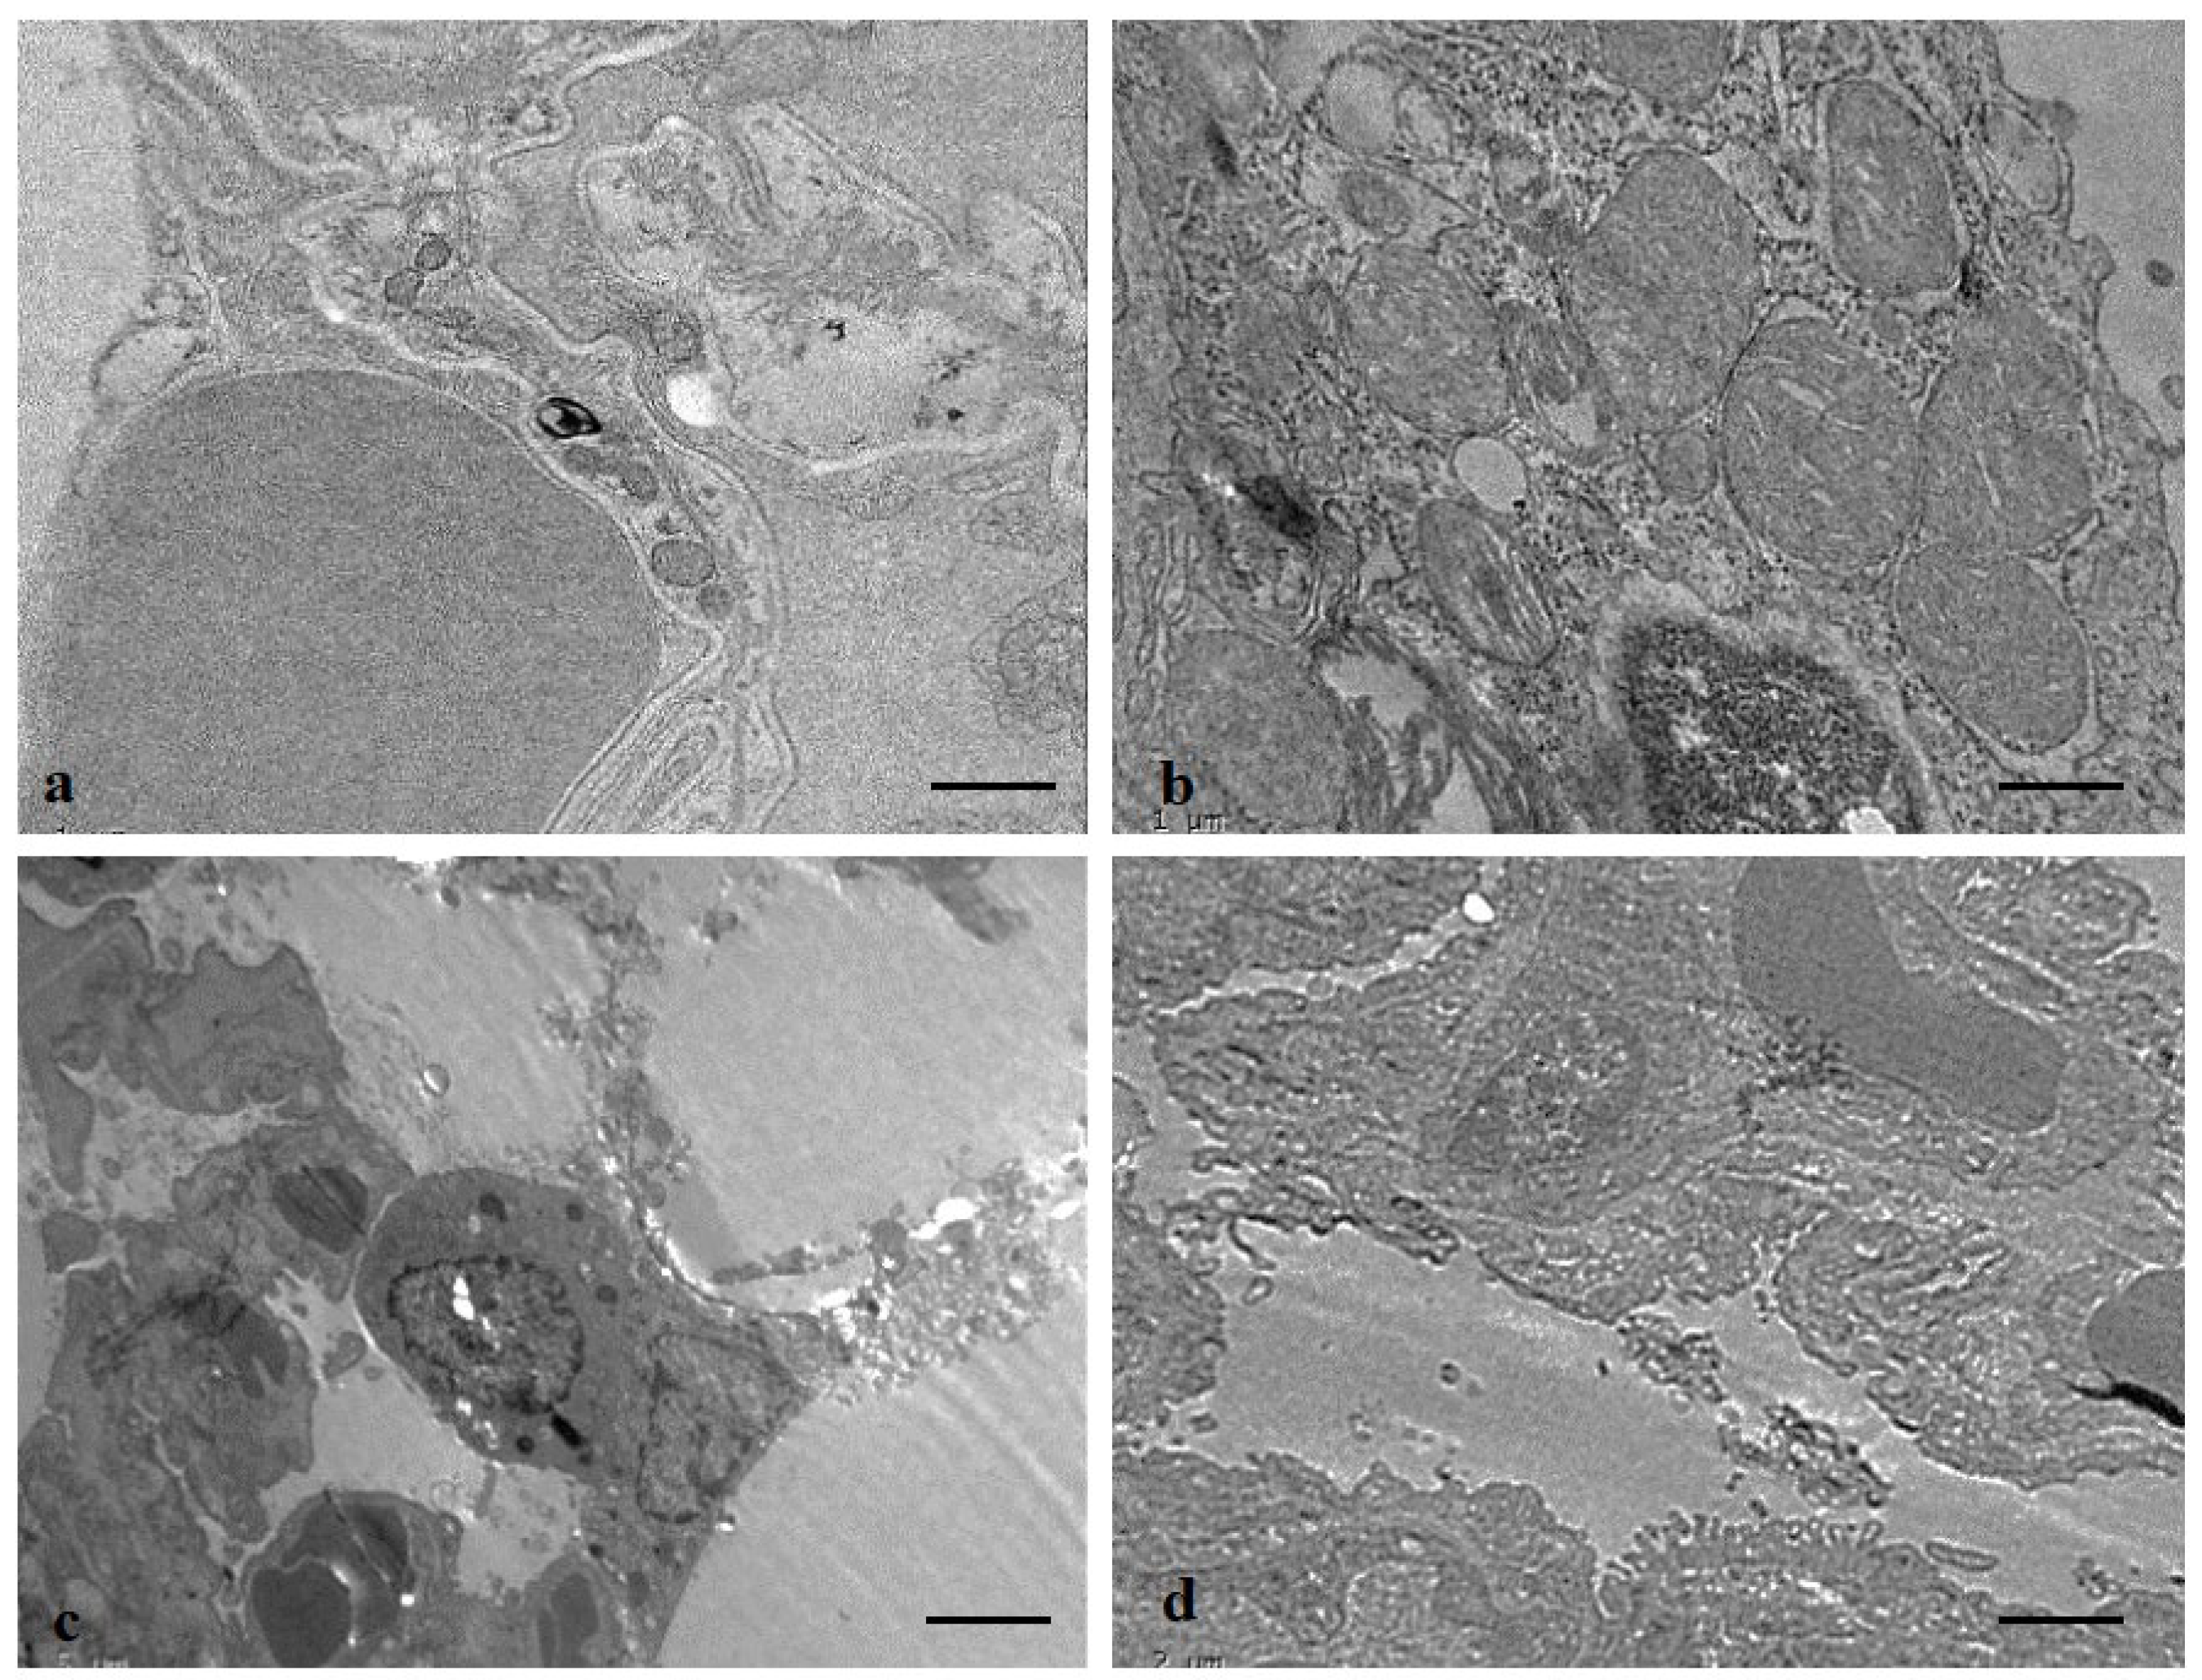

3.12. Protective Role of ADE on Lung Tissue Ultrastructure